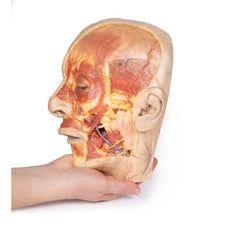

The head and neck of the specimen provides views of both superficial and deep structures in the region. The calotte has been removed ~2cm superior to the orbits to expose the brain in relation to the endocranial cavity. The transverse section through the cerebrum demonstrates the relation of the grey matter cortex to the white matter medulla, as well as the lateral ventricles with a small amount of choroid plexus visible in the base of both spaces. The skin and superficial fascia on the right side has been retained and false-coloured to display the angiosomes of the face and posterior neck. On the left side, the superficial tissues have been dissected to expose the muscles of facial expression, muscles of mastication, and deeper structures of the infratemporal fossa including the lingual nerve, terminal branches of the external carotid artery into the superficial temporal and maxillary arteries.

The carotid sheath has been opened on both sides of the neck, and the internal jugular veins and sternocleidomastoid muscles largely removed, to expose the pathway of the common carotid arteries, internal and external carotid arteries, and the vagus nerves. On the right side, the great auricular nerve ascends towards the face, while the hypoglossal nerve can be seen adjacent to the exposed stylohyoid ligament and supra- and infrahyoid muscles. A large thyroid gland is present bilaterally inferior to the thyroid cartilage, with a well-preserved superior thyroid artery and inferior thyroid vein on the right side and across the midline.

The head and neck of the specimen provides views of both superficial and deep structures in the region. The calotte has been removed ~2cm superior to the orbits to expose the brain in relation to the endocranial cavity. The transverse section through the cerebrum demonstrates the relation of the grey matter cortex to the white matter medulla, as well as the lateral ventricles with a small amount of choroid plexus visible in the base of both spaces. The skin and superficial fascia on the right side has been retained and false-coloured to display the angiosomes of the face and posterior neck. On the left side, the superficial tissues have been dissected to expose the muscles of facial expression, muscles of mastication, and deeper structures of the infratemporal fossa including the lingual nerve, terminal branches of the external carotid artery into the superficial temporal and maxillary arteries.

The carotid sheath has been opened on both sides of the neck, and the internal jugular veins and sternocleidomastoid muscles largely removed, to expose the pathway of the common carotid arteries, internal and external carotid arteries, and the vagus nerves. On the right side, the great auricular nerve ascends towards the face, while the hypoglossal nerve can be seen adjacent to the exposed stylohyoid ligament and supra- and infrahyoid muscles. A large thyroid gland is present bilaterally inferior to the thyroid cartilage, with a well-preserved superior thyroid artery and inferior thyroid vein on the right side and across the midline.